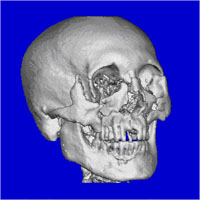

眶颧部的骨质缺损会使得上面部明显凹陷,严重影响外观。以下就是一幅额颞部缺损的正面照片。

图4 左侧额颞部颅骨缺损的正面观

(图片来自Journal of craniomaxillofacial surgery)